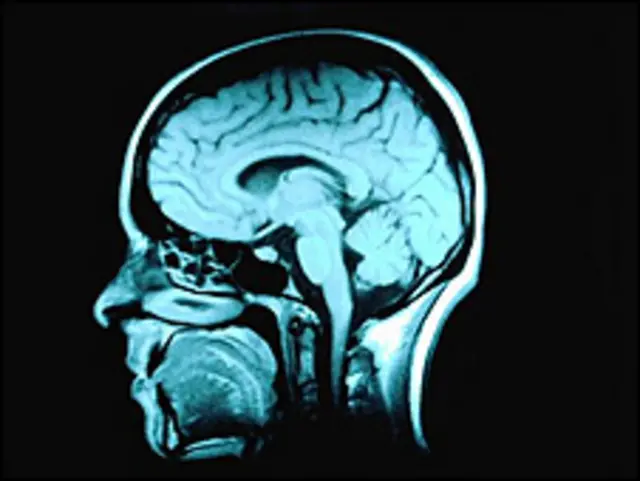

多吃维生素B可减少大脑萎缩

牛津大學的科學家對168人進行的試驗研究,發現每日服用大劑量的維生素B葉酸、維生素B6和維生素B12,能減少大腦萎縮最多達53%,大腦萎縮是失智症的明顯症狀。

大腦萎縮

一般人年過60歲以後大腦開始自然萎縮,醫學界相信萎縮速度大概是一年最多0.5%。

但是有輕度認知損害(MCI)症狀的人大腦萎縮速度達一年1%。

阿茲海默症(Alzheimer's disease)患者的大腦萎縮速度更快,一年最多萎縮2.5%,患者出現嚴重的記憶喪失和思考緩慢。